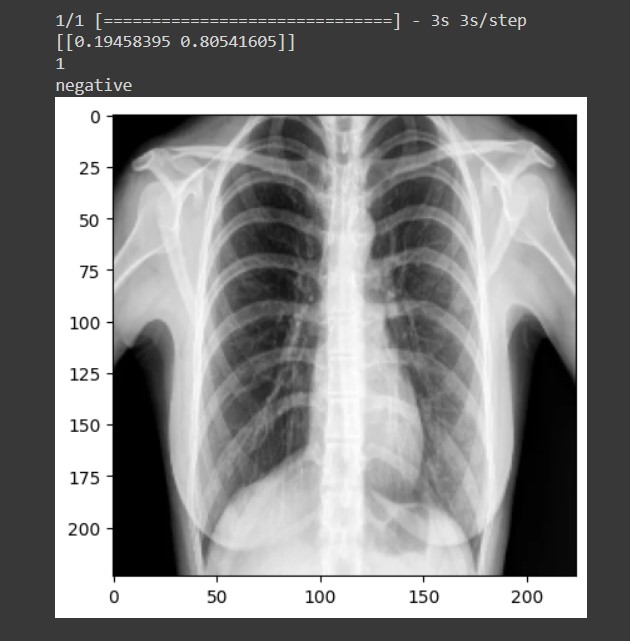

Millions of people are infected by the coronavirus disease 2019 (COVID-19) around the world. Within three months of its first report, it rapidly spread worldwide with thousands of deaths. Since that time, not only underdeveloped and developing countries, but also developed countries have suffered from insufficient medical resources and diagnoses. In this circumstance, researchers from medical and engineering fields have tried to develop automatic COVID-19 detection toolkits using machine learning (ML) techniques. The dataset is the fundamental element of any detection tool therefore, most of the ML-based COVID-19 detection research was conducted used chest x-ray and computed tomography (CT) image datasets. Our aims is to build a Machine Learning based system to detect covid19 using chest xray images efficiently and effectively. In our machine learning model we use mobileNet architecture to train a dataset with 648 chest xray images with 2 classes ‘Normal’ and ‘COVID’ and we achieve 97% of accuracy.